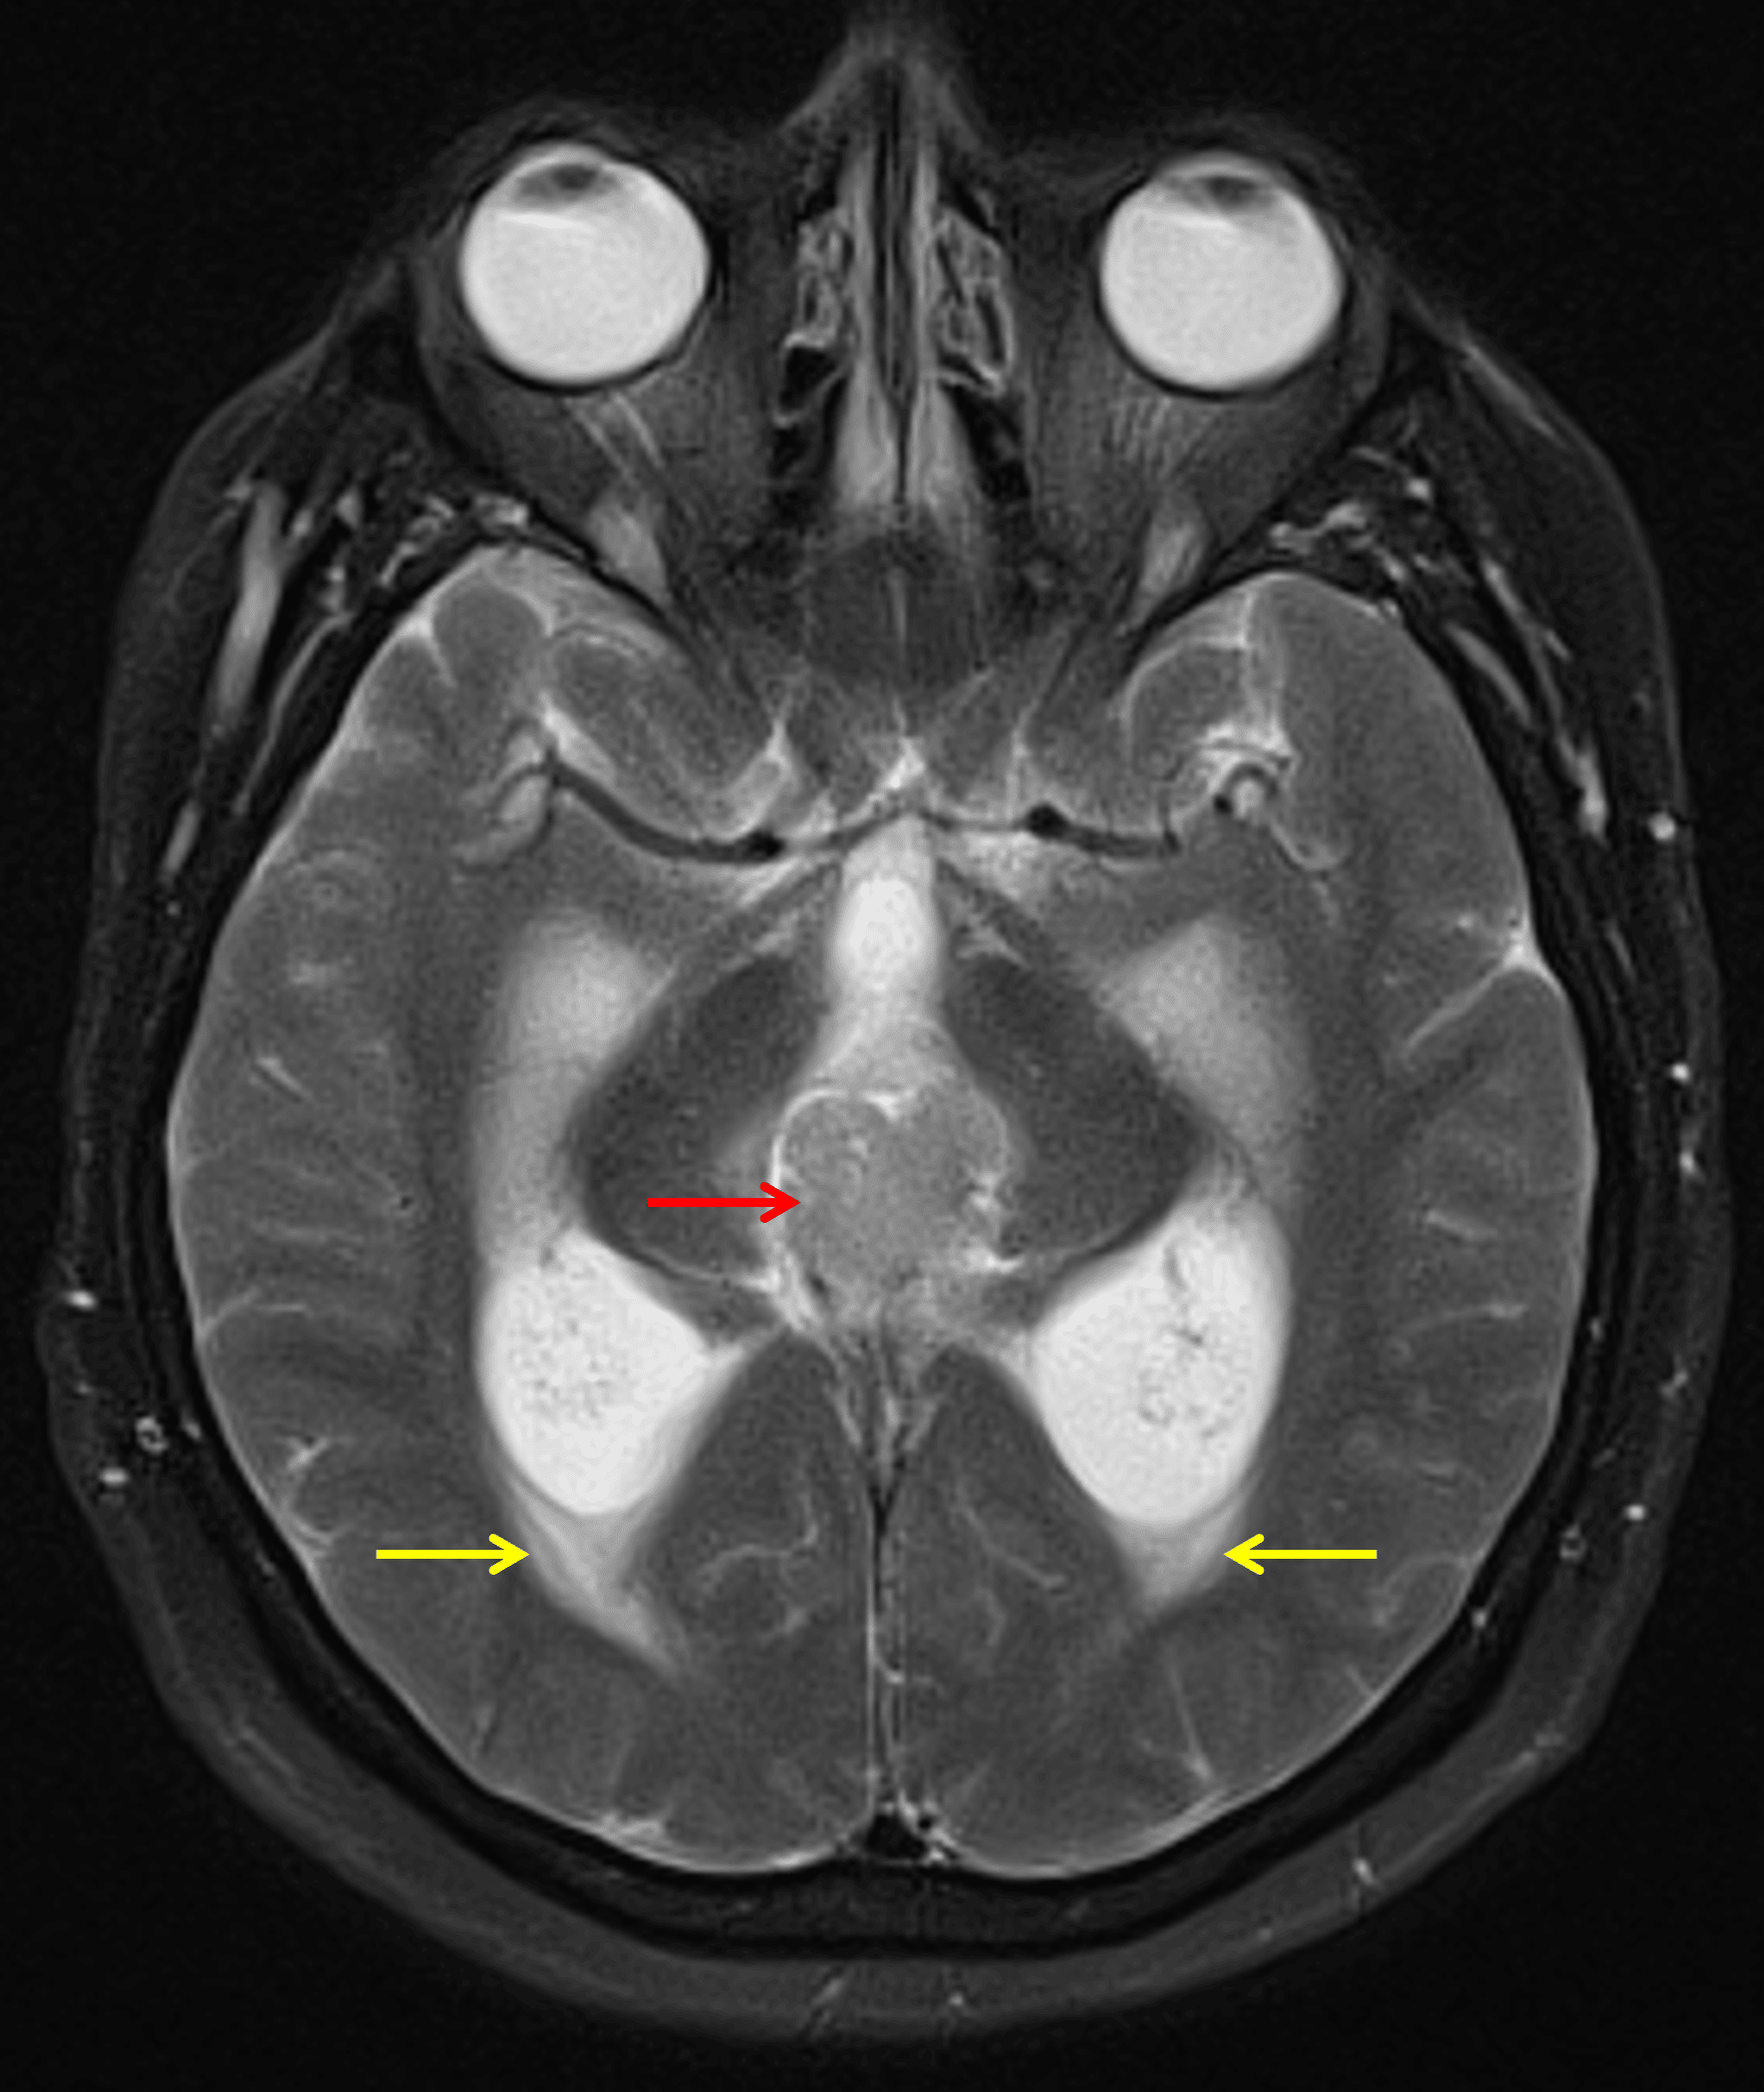

MRI

- Pineal region mass measuring 3.3 x 2.5 x 2.5 cm

- Diffuse intermediate T2 signal, restricted diffusion, and avid enhancement

- Peripheral foci of susceptibility artifact corresponding to calcification on the CT

- Downward mass effect on the tectum with obstructive hydrocephalus at the level of the cerebral aqueduct and subependymal edema

The mass demonstrates intermediate T2 signal intensity (red arrow). There is associated obstructive hydrocephalus with subependymal edema (yellow arrows).